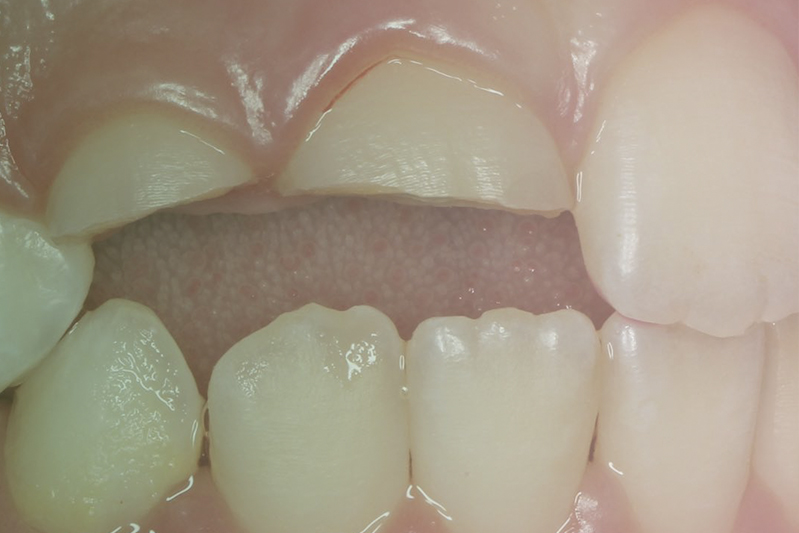

Клинический случай. Терапия

10 апреля 2020